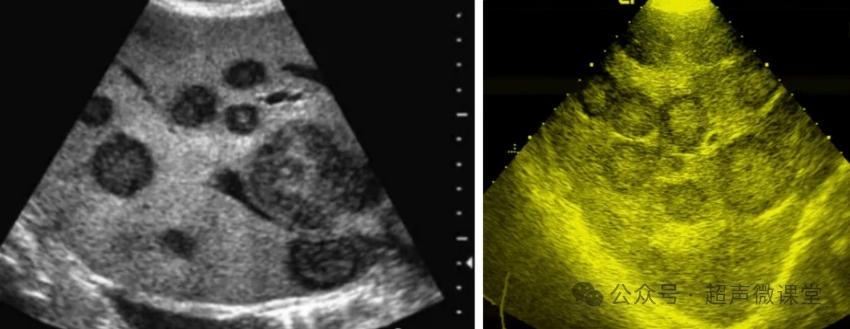

转移性肝癌

葡萄胎